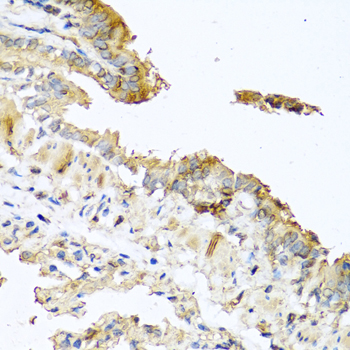

Immunohistochemistry of paraffin-embedded human prostate using RNASE11 antibody at dilution of 1:100 (40x lens).

Immunohistochemistry of paraffin-embedded mouse lung using RNASE11 antibody at dilution of 1:100 (40x lens).